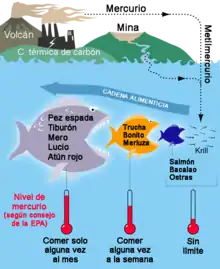

O consumo de peixes e frutos do mar são a principal fonte de contaminação indireta por humanos e animais carnívoros. Como o mercúrio não é biodegradável, vai se acumulando nos corpos de organismos e transferido cada vez mais acima na cadeia alimentar, por bioacumulação. Logo, animais que se alimentam de peixes podem se contaminar com o mercúrio presente nesses indivíduos, transferindo-o para humanos quando são consumidos (magnificação trófica). Em peixes, aqueles mais acima na cadeia alimentar têm, geralmente, níveis mais elevados de mercúrio.

Até plantas e animais herbívoros podem ser afetados devido a bioconcentração de mercúrio na água do mar, na água doce, em sedimentos e na atmosfera, mas em um grau cem vezes menor que peixes carnívoros.[8]

Os peixes com mais concentração de mercúrio e que devem ser consumidos menos de uma vez por mês e evitados por grávidas e lactantes são[9]:

- Cavala (rei ou espanhola);

- Marlim;

- Peixe-relógio;

- Tubarão;

- Peixe-espada;

- Pirá;

- Atum;

- Anchova;

- Garoupa;

- Achigã.